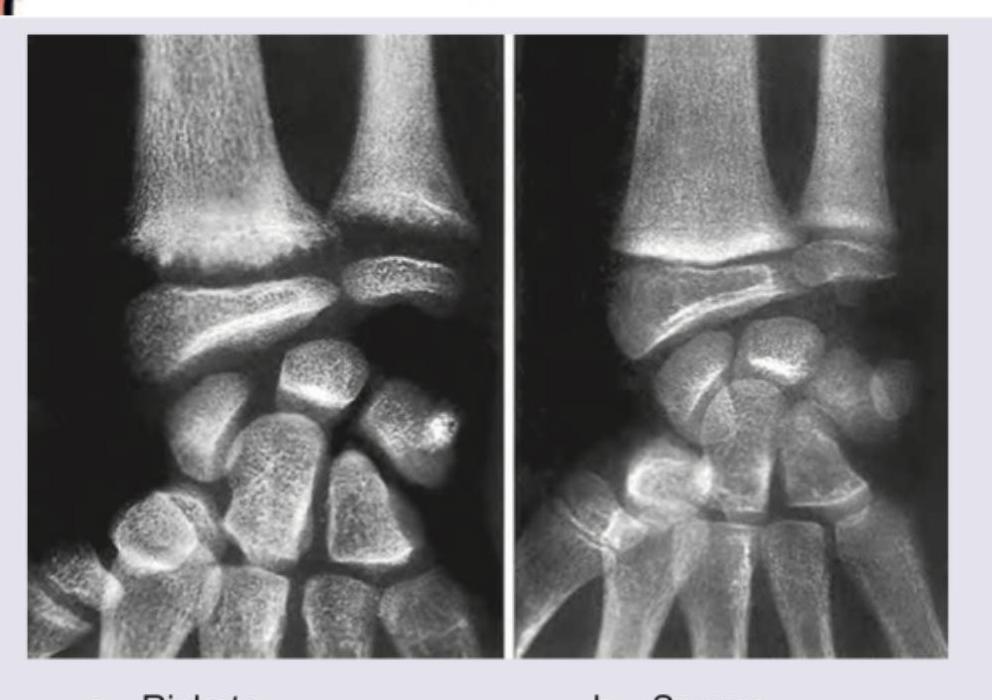

Explanation: **This is an EXCEPT question** - three statements are WRONG, one is CORRECT. ***Loss of normal zone of provisional calcification adjacent to metaphysis*** ✓ **CORRECT STATEMENT** - This is a **true statement** and the correct answer to this EXCEPT question. - The image shows findings consistent with **rickets**, characterized by **widened, irregular growth plates** at the wrists. - The **zone of provisional calcification** is where cartilage is normally mineralized before ossification; its loss or irregularity is a **hallmark radiological finding of rickets**. - This occurs due to inadequate calcium and phosphorus for proper mineralization. *Nutritional rickets usually presents in school age, usually as widened wrists* - **WRONG STATEMENT** - This statement is **FALSE** (making it incorrect for this EXCEPT question). - Nutritional rickets typically manifests in **infancy or early childhood (3 months to 3 years)**, NOT school age. - While widened wrists are indeed a clinical feature, the age of presentation stated here is incorrect. - School-age presentation is more typical of **X-linked hypophosphatemic rickets**, not nutritional rickets. *Presentation in early infancy along with seizures or tetany* - **WRONG STATEMENT** - This statement is **FALSE** (making it incorrect for this EXCEPT question). - While seizures or tetany CAN occur in rickets due to **severe hypocalcemia**, they represent **complications**, not typical initial presentations. - Typical early presentations include **craniotabes** (skull softening), delayed fontanelle closure, frontal bossing, and rachitic rosary. - Seizures/tetany occur only in severe cases with marked hypocalcemia. *Excessive exposure to sunlight does not increase vitamin D production* - **WRONG STATEMENT** - This statement is **FALSE** (making it incorrect for this EXCEPT question). - Sunlight exposure **DOES increase vitamin D production** - this is well-established physiology. - **UVB radiation** converts 7-dehydrocholesterol in skin to previtamin D3, which isomerizes to vitamin D3. - Sunlight is the **primary natural source** of vitamin D synthesis in humans.

Explanation: ***Rickets*** - The image displays characteristic radiographic findings of **rickets**, including **fraying, cupping**, and **widening of the metaphyses**, particularly evident at the distal radius and ulna. - These changes result from impaired mineralization of growing bone and cartilage at the **growth plates** due to vitamin D deficiency in children. *Scurvy* - Scurvy, caused by vitamin C deficiency, affects **collagen synthesis**, leading to subperiosteal hemorrhages and thinning of the cortex. - Radiographic features include a **dense metaphyseal line (Wimberger's sign)** and **epiphyseal separation**, which are not the primary features seen here. *Osteomalacia* - **Osteomalacia** is the adult form of rickets, characterized by defective mineralization of bone matrix. - While it features **pseudofractures (Looser zones)** and generalized osteopenia, it does not present with growth plate abnormalities like fraying and cupping, as growth plates are typically closed in adults. *Osteoporosis* - **Osteoporosis** involves a reduction in bone mass and density, leading to increased bone fragility and fracture risk. - Radiographically, it manifests as generalized **osteopenia** and trabecular thinning, without the specific metaphyseal irregularities seen in rickets.